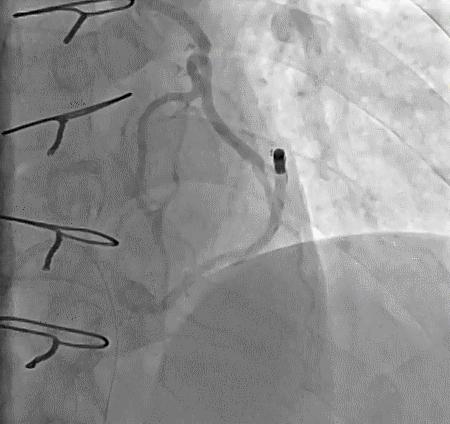

(3)冠状动脉静脉桥血管

首选导管:JR4.0;

其他导管:AL 1.0;AR 1.0

操作:升主动脉造影,寻找静脉桥血管

➢ CASE 3

AL1.0

➢ CASE 4

➢ CASE 5

升主动脉造影未见桥血管显影,原位血管造影也没发现竞争血流迹象,可以确定桥血管已闭塞,必要时可以借助冠脉CTA辅助诊断